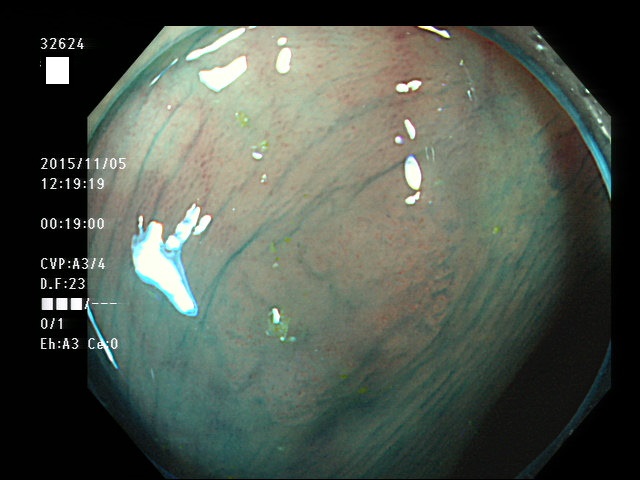

32603 32604 32605 32606 32607 32611 32614 32615 32616 32619 32620 32621 32623 32624 32625 32630 32631 32632 32635 32637 32638 32639 32641 32642 32649 32650 32651 32653 32654 32656 32657 32658 32661 32662 32663 32664 32665 32666 32669 32671 32673 32674 32675 32679 32681 32682 32683 32685 32686 32688 32689 32690 32695 32696 32698 32699・・・・・・の56名

上記100名より抽出した平坦・陥凹型腺腫(=癌化の危険が高いが見落としやすい病変)の内視鏡写真